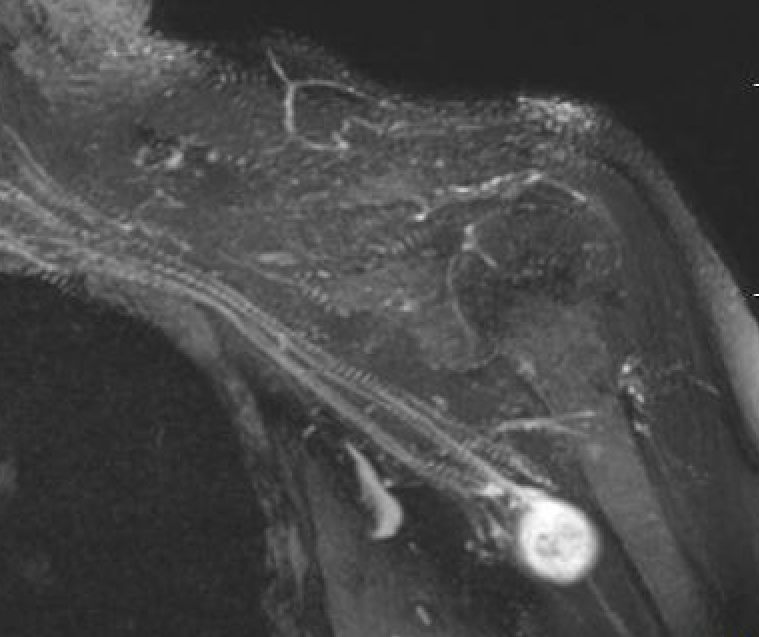

MRI

Target sign

- hypointense centrally

- hyperintense peripherally

Neurofibroma brachial plexus